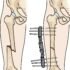

Intramedullary Nailing

- For femoral shaft fractures, reduction and intramedullary nailing are currently recommended.[rx] The bone is re-aligned, then a metal rod is placed into the femoral bone marrow, and secured with nails at either end. This method offers less exposure, a 98%-99% union rate, lower infection rates (1%-2%) and less muscular scarring.[rx][rx][rx]

- Currently, the method most surgeons use for treating femoral shaft fractures is intramedullary nailing. During this procedure, a specially designed metal rod is inserted into the canal of the femur. The rod passes across the fracture to keep it in position.

An intramedullary nail can be inserted into the canal either at the hip or the knee. Screws are placed above and below the fracture to hold the leg in correct alignment while the bone heals.

Intramedullary nails are usually made of titanium. They come in various lengths and diameters to fit most femur bones.